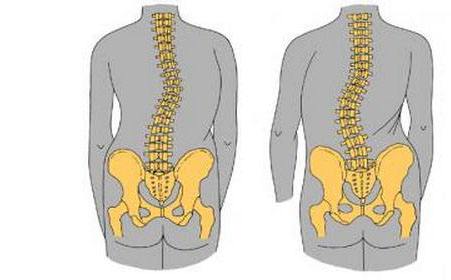

强直性脊柱炎以骶髂关节和脊柱附着点炎症为主要症状的疾病。与HL ...

强直性脊柱炎,是一种原因不明的、以中轴关节慢性炎症为主的全身 ...